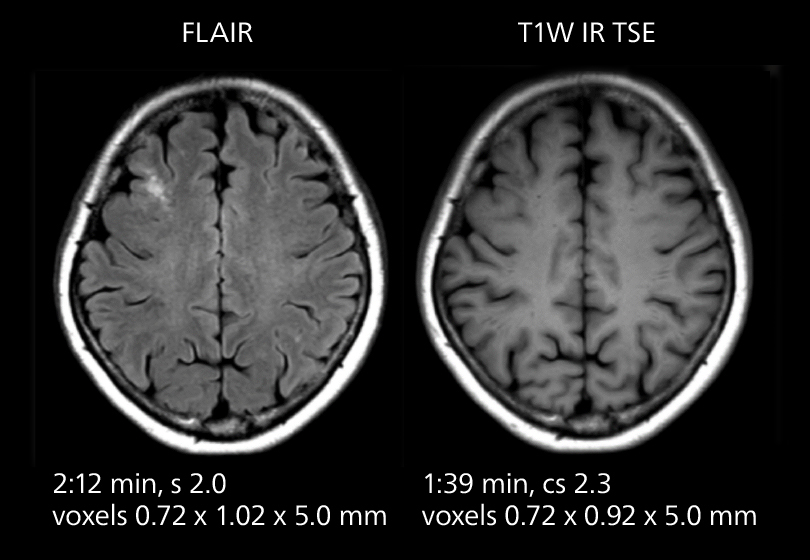

These images of an old cerebral infarction demonstrate the speed and image quality after upgrading to Elition X.